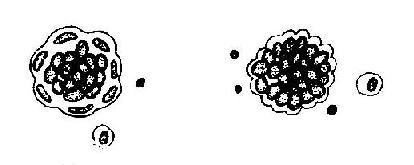

(1)腺癌细胞:①大细胞型腺癌:是最为常见的形态,细胞体积大,呈圆形或卵圆形。胞质嗜碱性,常散在或聚集成团。胞质内出现粘液空泡。胞质呈圆形或卵圆形,体积大,染色质呈粗网状或粗颗粒状,染色深。可见一个或多个畸形核仁,直径可达4-5μm .。可出现印戒细胞、癌巨细胞或多核癌巨细胞,常见病理性核分裂像,这种癌巨细胞常混杂于成团脱落癌细胞中。癌细胞团中央可出现空隙腔样结构;或癌细胞团中央部细胞染色较淡。边缘癌细胞及胞核呈不规则扁平状,染色深而胞质少,呈镶边样结构(图21-19)。②小细胞型腺癌:癌细胞体积较小,直径约12-20μm。胞质较少,嗜碱性淡紫红染色,有的胞质内见粘液空泡,胞核为不规则圆形或卵圆形,有明显畸形,染色深有的呈墨水滴样。癌细胞常成团排列紧密中央部癌细胞核常堆叠挤压,边级部癌细胞随胞核而向表面隆起,呈桑椹样结构;有的癌细胞团周围包绕一圈少量胞质,核深染,呈镶边样结构(图21-20)。

图21-19 浆膜腔积液内大细胞型腺癌癌细胞示意图

图21-20 腹膜腔积液内小细胞型腺癌细胞示意图